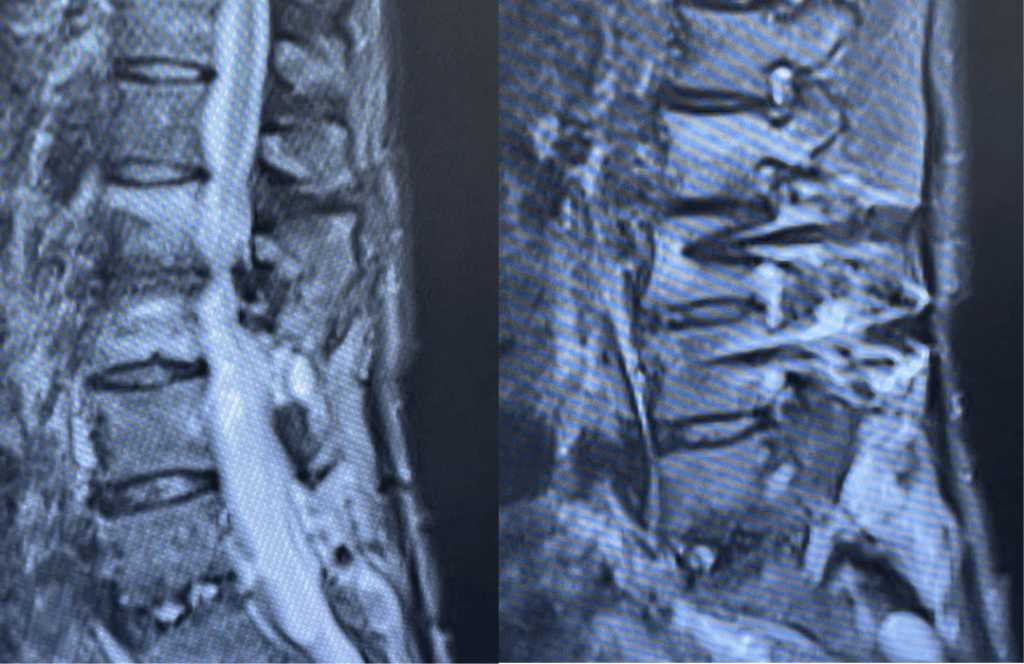

During the decompression we removed the inferior facets of L2 after the L3 screws were removed. This is a key maneuver in a revision decompression as it allows access to a dissection plane that allows the foramina and both L3 nerve roots to safely be decompressed. The L2 lamina is removed as well as a dissection plane at the inferior aspect of the bone is developed with an up biting curette. Because of her solid fusion it was only necessary to add new screws at L2 and L3 giving her a shorter construct and less potential stress at the next segment. Post operatively the patient did very well with resolution of leg pain and improved strength in her proximal leg (Figure 3).

Figure 3. Post Op AP and lateral x-rays after L2-3 instrumented fusion